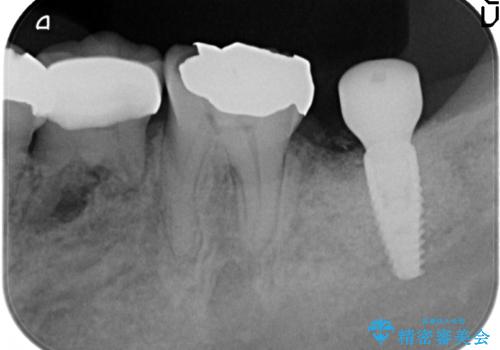

歯の破折による抜歯 インプラントによる咬合機能回復

- 左下奥歯の咬合時疼痛を訴えて来院されました。

最後方臼歯周囲には大きな透過像が見られ、破折が強く疑われること抜歯が想定されることを理解していただき銀歯を除去したところ破折が認められたため抜歯を行いました。

今後の機能回復方法としてインプラント治療を希望されたため、将来的に大規模な骨造成が必要とならないよう歯槽堤保存術を抜歯と同時に行いました。

術前、歯の破折により大きな骨の吸収が認められていたため骨量を十分に回復するために抜歯と同時に歯槽堤保存術を行い十分な骨量の回復をすることができました。